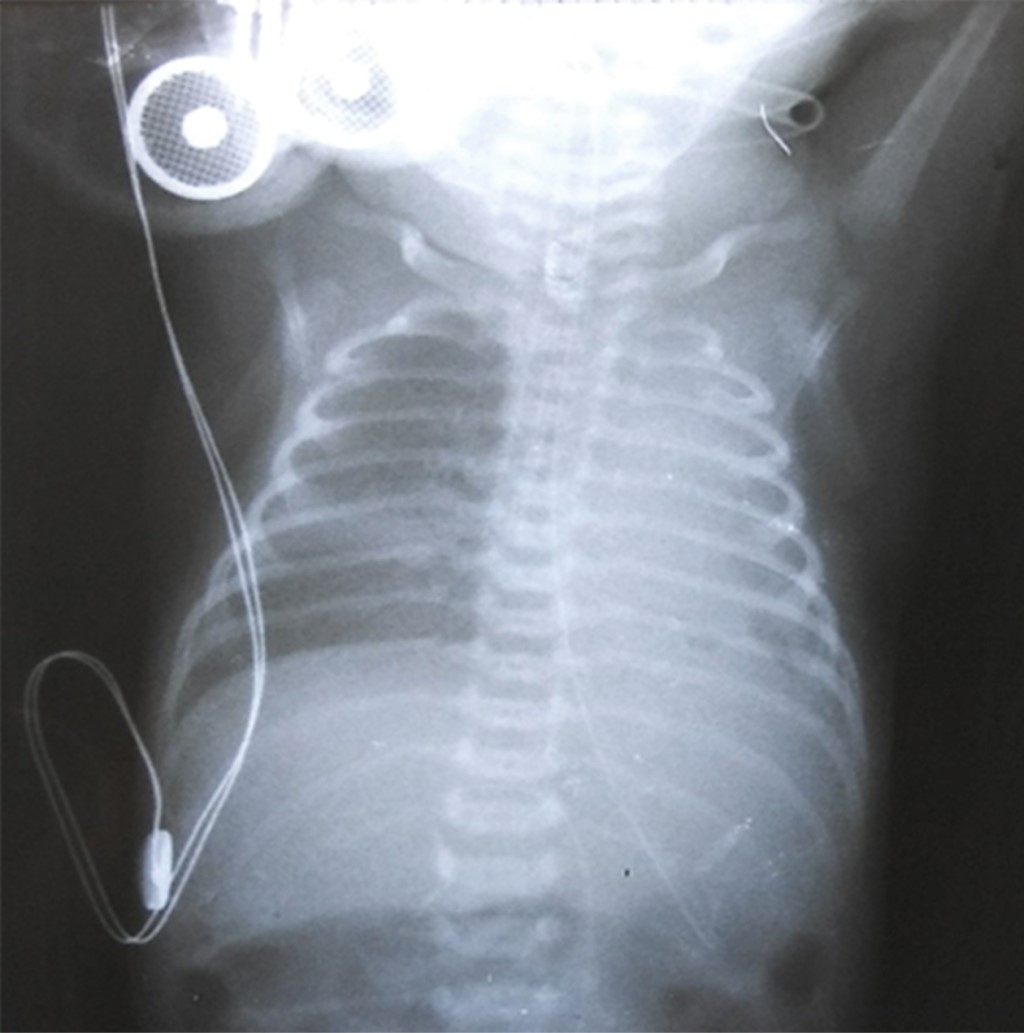

Unilateral interstitial pulmonary emphysema in a newborn

Objective: To describe the clinical outcome of a newborn (NB) with unilateral pulmonary interstitial emphysema (PID) who required selective ventilation of the contralateral lung. Case presentation: This is a 32-week gestation female newborn, who presented respiratory distress syndrome (RDS), requiring mechanical ventilation. On the second day of life, she presented left unilateral interstitial PID. High-frequency oscillatory ventilation was used as treatment for this complication, as well as positioning of the newborn on the affected side, but there was no improvement. Subsequently, after selective ventilation of the contralateral lung was used for 48 hours total resolution of the emphysema was achivied. Conclusion: PID is a serious complication in newborns. The use of selective ventilation to the contralateral lung is a therapeutic alternative for its resolution.

Figure 3